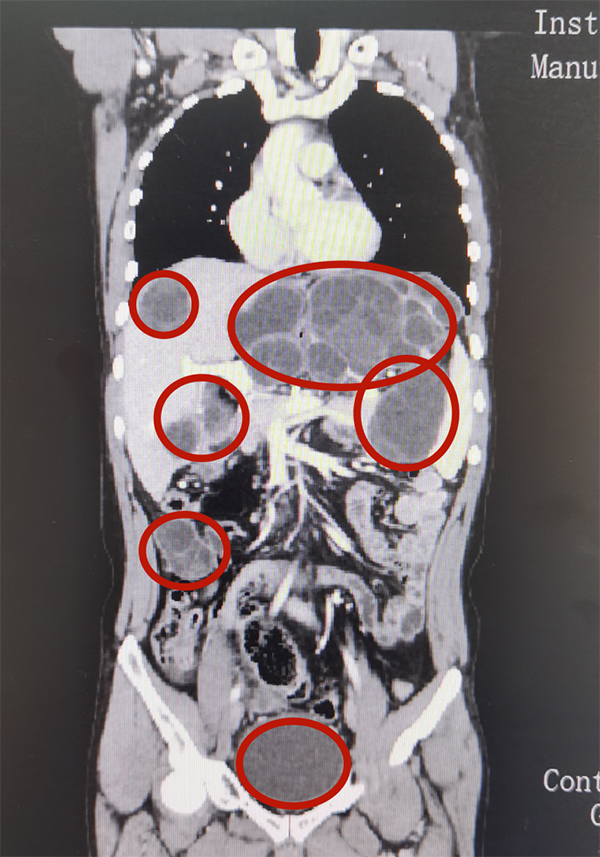

新婚不久的图尔逊今年32岁,两个星期前反复地出现腹部疼痛不适,遂在当地医院接受了腹部CT检查。检查结果把接诊医生吓了一跳:只见图尔逊的腹腔中有大大小小20余个肿块,最大的位于左上腹脾门区,长径近20厘米。肝脏上最大肿块直径也将近15厘米,其它的肿块大小不一,分布在腹腔各处。

结合影像学和实验室检查结果,医生考虑图尔逊患上了腹腔多发包虫病,且已累及肝脏、胰腺、脾脏、胃、肠道等多个脏器。由于情况非常严重和复杂,图尔逊来到了喀地一院肝胆胰腺外科寻求帮助。

患者术前CT片(红圈所示为腹腔内部分包块)